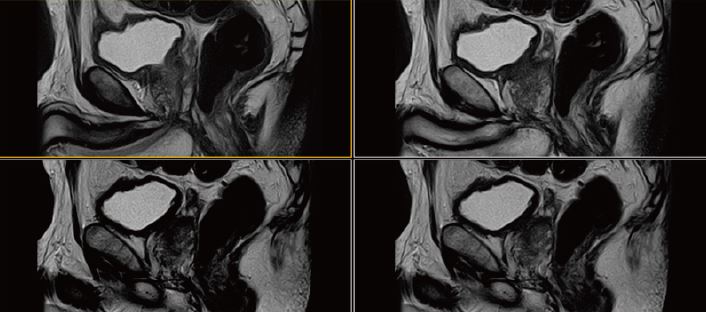

Рис. 5. Сагітальне,  Т2-зважене зображення.

Рис. 6. Аксіальне, Т2-зважене зображне (за протоколом mpMR).